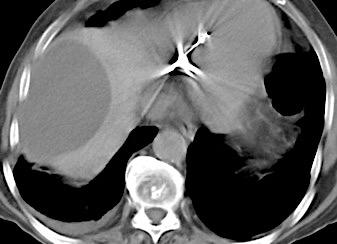

Hemorrágica………….30-70 UH

Extravasación iv. con sangrado activo……….>90 UH

“Simpático”………….,,,,<15 UH

Durso AM et al. Penetrating Thoracic Injury. Radiol Clin N Am 2015.

Urogénico……………….< 15 UH

Entérico.. ………………+/- 15UH

Biliar, Quiloso……………..<0 UH

Abramowitz1 Y et al. Pleural Effusion: Characterization with CT Attenuation Values and CT Appearance .AJR 2008